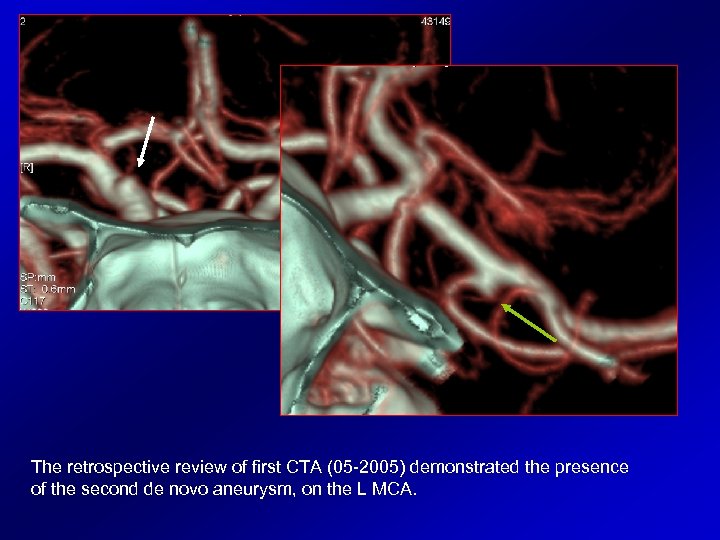

First follow up CTA (05 -2005) demonstrated a de novo lesion located on the ophthalmic R ICA (white arrows).

Last CTA (02 -2009) shows slight progressive increase of the aneurysm located on R ICA, also depicting another, smaller lesion on the trifurcation of L MCA (green arrows).

The retrospective review of first CTA (05 -2005) demonstrated the presence of the second de novo aneurysm, on the L MCA.